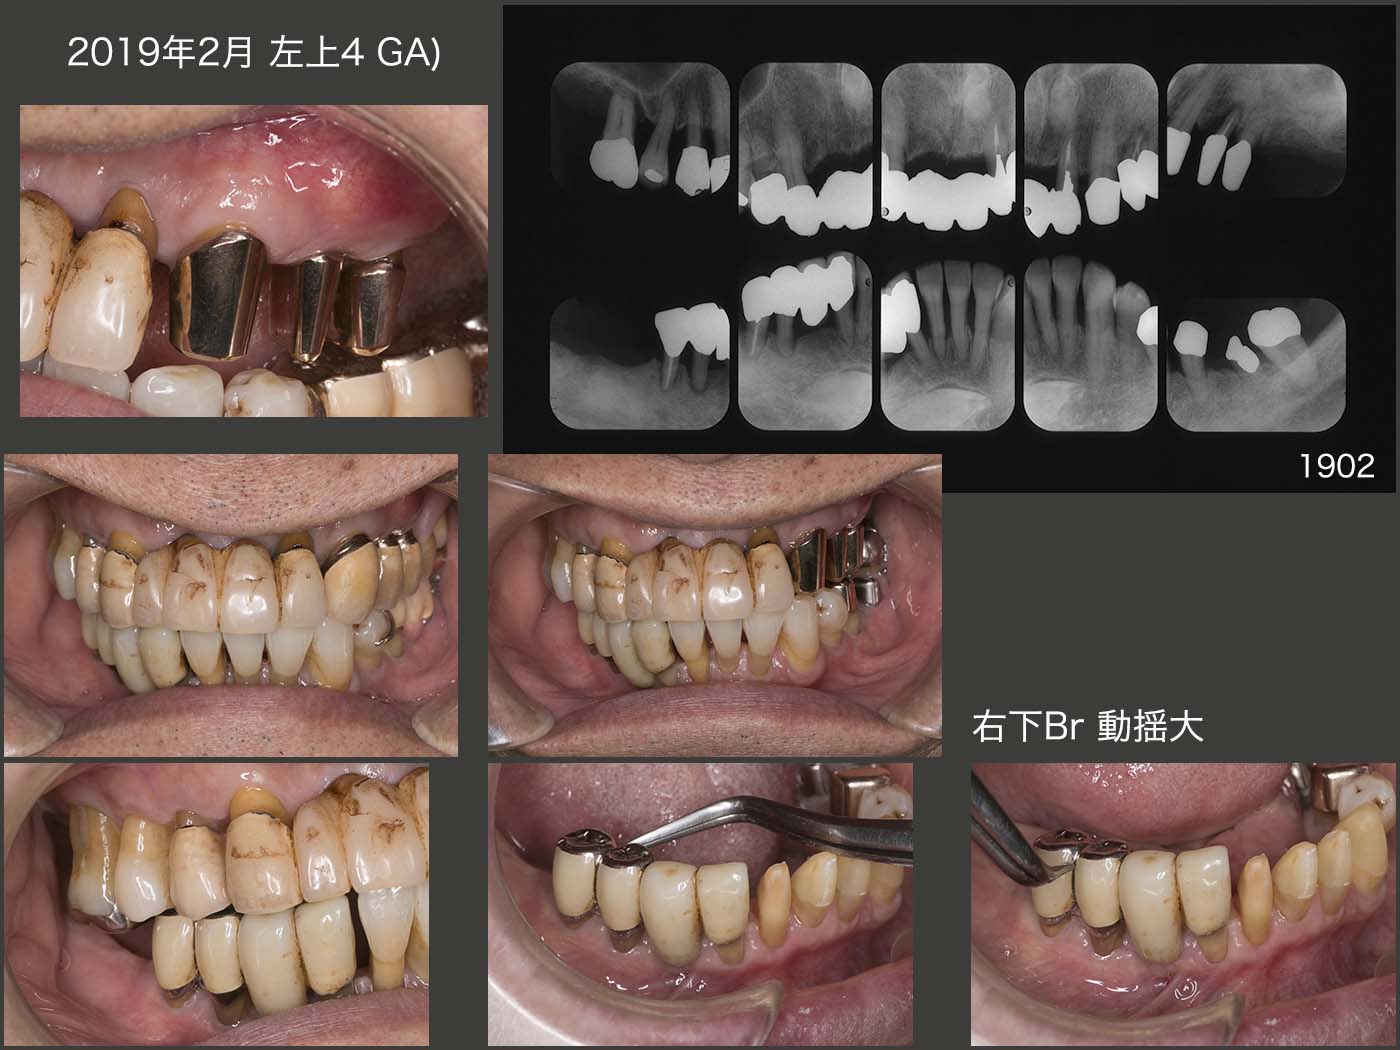

しかし,2019年2月,左上4に歯根破折によると思われる歯肉膿瘍が生じ,左側の歯の咬合・咀嚼力に対する荷重負担を伺わせた.このままでは,順次左側の咬合支持歯を失っていくサイクルに突入すると考え,何とか右側でも咀嚼できるようになる手立てはないかと熟慮した.

そこでまず,下顎前歯を取り込んで連結固定することで,右下のブリッジの動揺が収まるかの検討を行いたく,患者さんにその旨をお伝えし,了承を得た.

下顎前歯と元の右下ブリッジの支台歯とを連結固定することで,動揺は何とか収まったように見受けられた.しかし,右側で咀嚼できるかと言ったらやはり心配であった.そこでもう一回,右下6部にインプラントを植立する計画を立て,実行した.今回は直径3mmの細いインプラントを使用し,インプラントで咀嚼するというより,あくまでも前方の支台歯と連結固定することで,支台歯の動揺が減少することを一番に期待した.